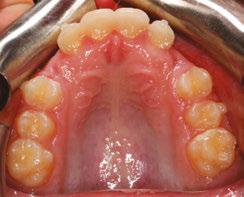

This patient presented in mixed dentition and a Class I occlusion with mild upper spacing, lower moderate crowding, and mild deep bite. The U3s were ectopic with a palatal position and a mesial path of eruption, converging onto the U2 roots, and the patient also had a tapered upper archform, an ovoid lower

archform, and a posterior tongue tie (mid-tongue restriction). The upper midline was centered with the facial midline, but the lower midline was deviated 4 mm to the left of the upper (Figure 1).

Figure 1: JA initial photos. Mixed dentition, Class I, upper spacing, lower crowding, ectopic U3s (10.7 years old)

Figure 3: Upper occlusal of the initial set-up versus upper occlusion clinical photo at 4 months